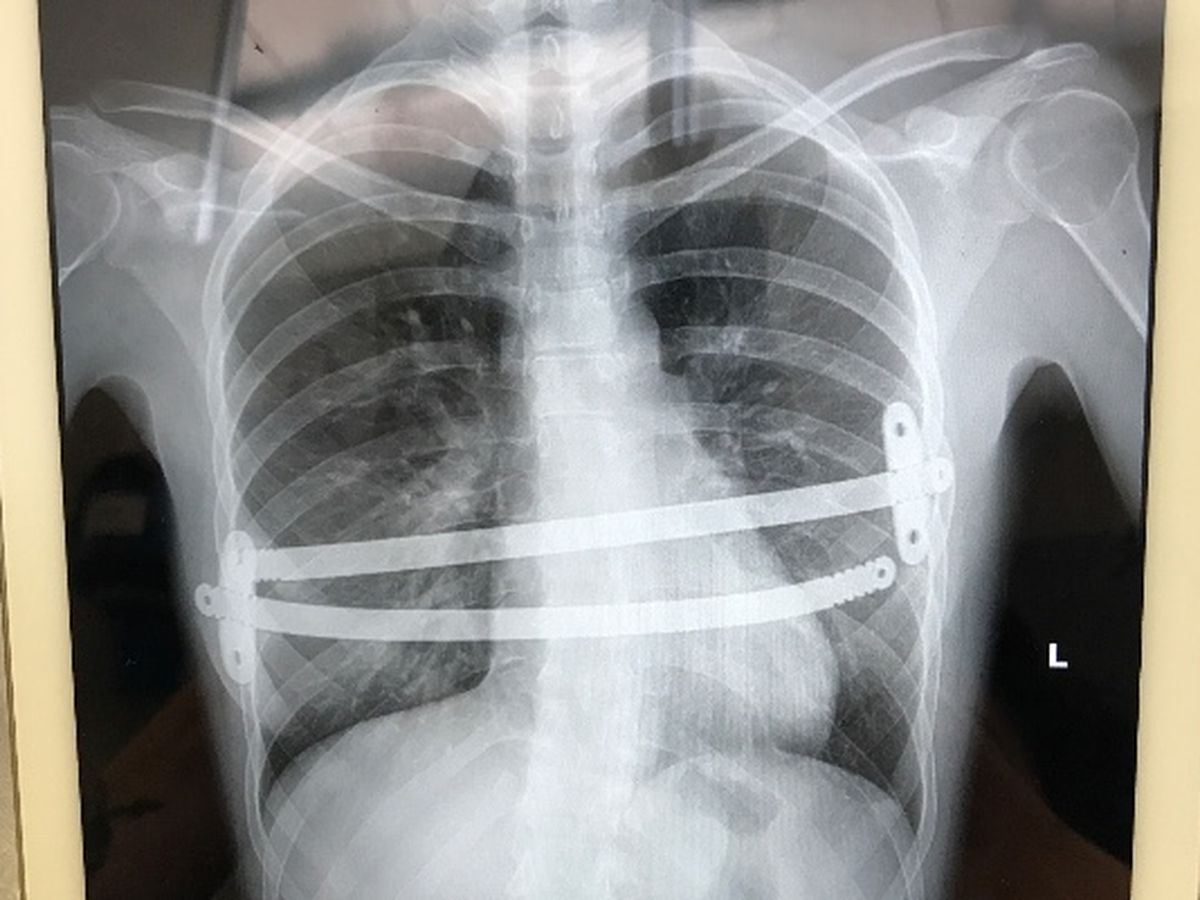

2 years ago I had corrective surgery to fix my condition called pectus. My sternum was growing inwards causing multiple medical problems such as bronchitis, pneumonia, sepsis, etc. It was a very serious life changing procedure. My sternum was broken into multiple pieces then two titanium rods were screwed to my ribs and it held my sternum in place of how it needed to regrow. Also while I was having my surgery my doctor discovered my heart and lung had grown together by 4 tendons causing major stress on my heart so those tendons were removed and now they are separate. I've been on pain medication for two years now to deal with the pain and so far so good.

Except now. My titanium bars have come undone and are pinching me internally and the pain is so unbearable I can't get myself up and out of bed. No one is sure exactly what caused this, some doctors believe the stress of the bars on my ribs overtime just snapped.